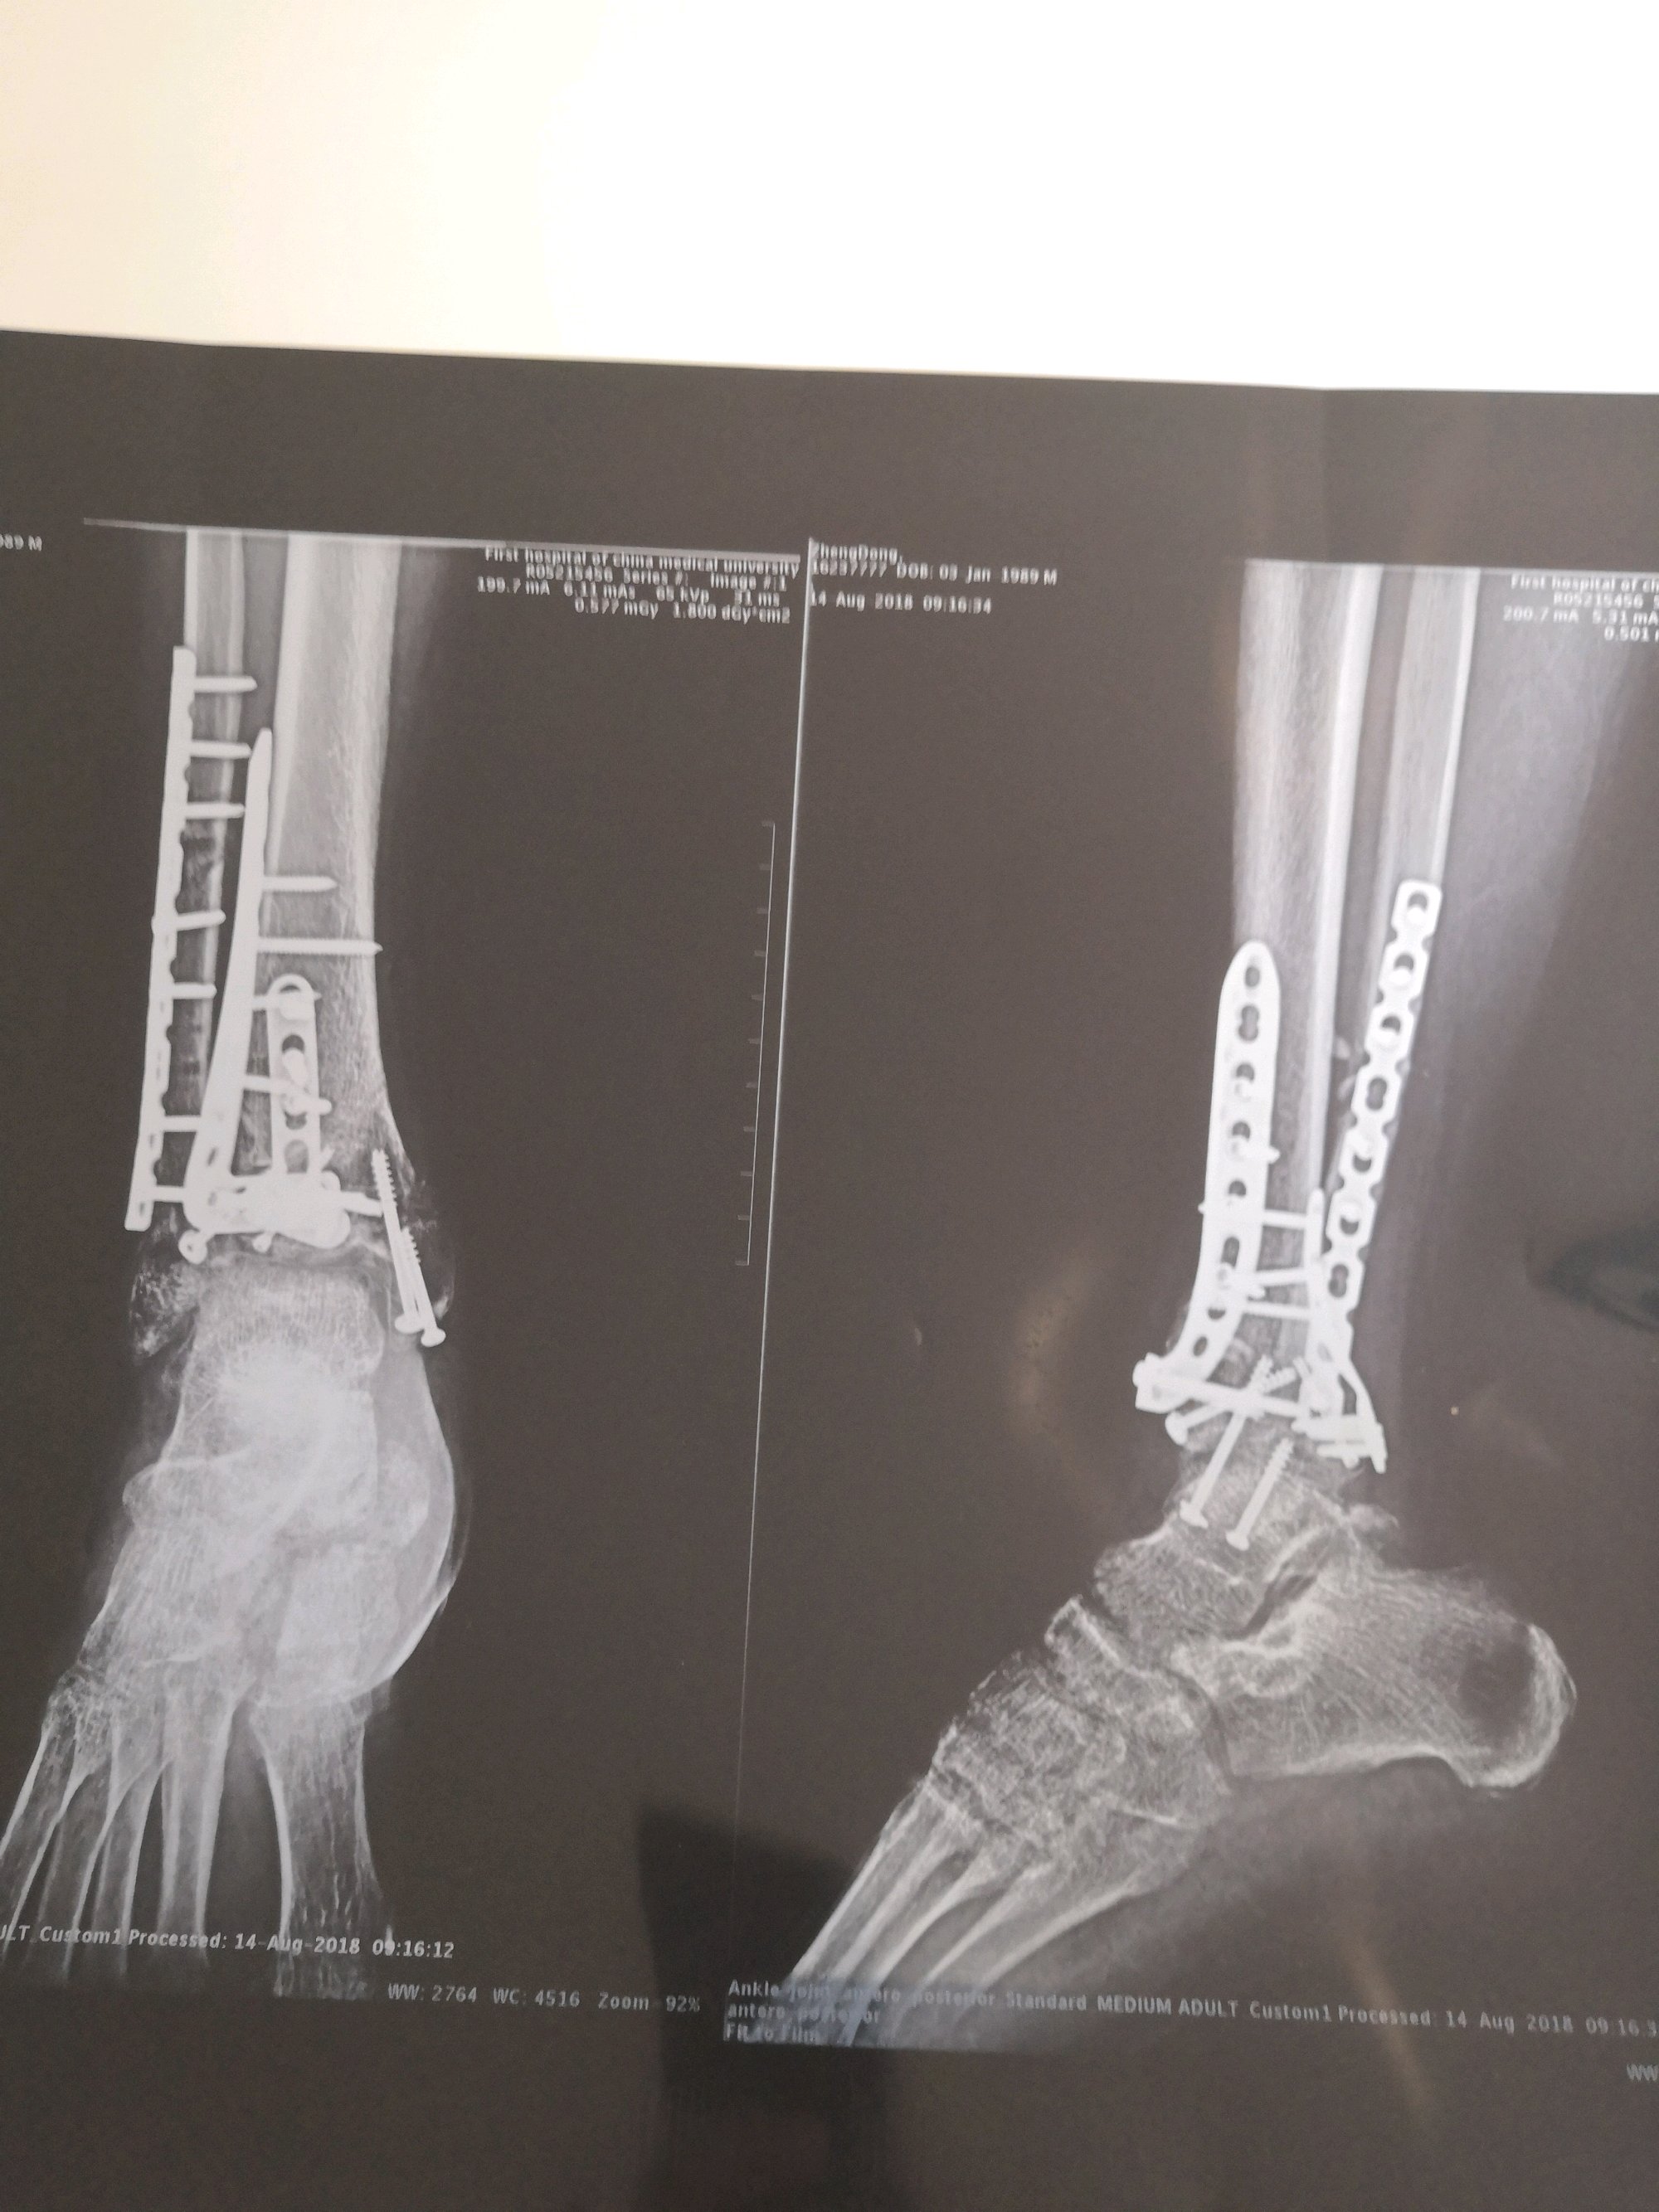

18年5月3日车祸,导致脚踝粉碎性骨折,面部多发性骨折,导致鼻子闻不到味道。大家看看我这个能鉴定到几级

伤残鉴定吧

这是我的片子

十级肯定稳,九级几率也很大